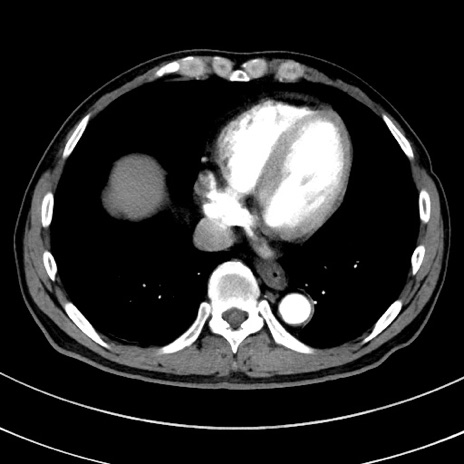

症例8(横断像)

【症例】 60歳代男性

【主訴】 黒色吐物

【現病歴】 4日前から嘔気自覚、2日前の朝食後にも嘔気あり、自分で手で嘔吐反射起こし嘔吐したところ血が混ざっていたため受診。

【既往歴】 5年前汎発性腹膜炎を伴う急性虫垂炎で手術、高血圧、前立腺肥大症、高脂血症

【身体所見】 腹部正中に手術癩痕あり 腹部平坦・軟圧痛なし膨満感あり

【データ】WBC 8400、CRP 4.54